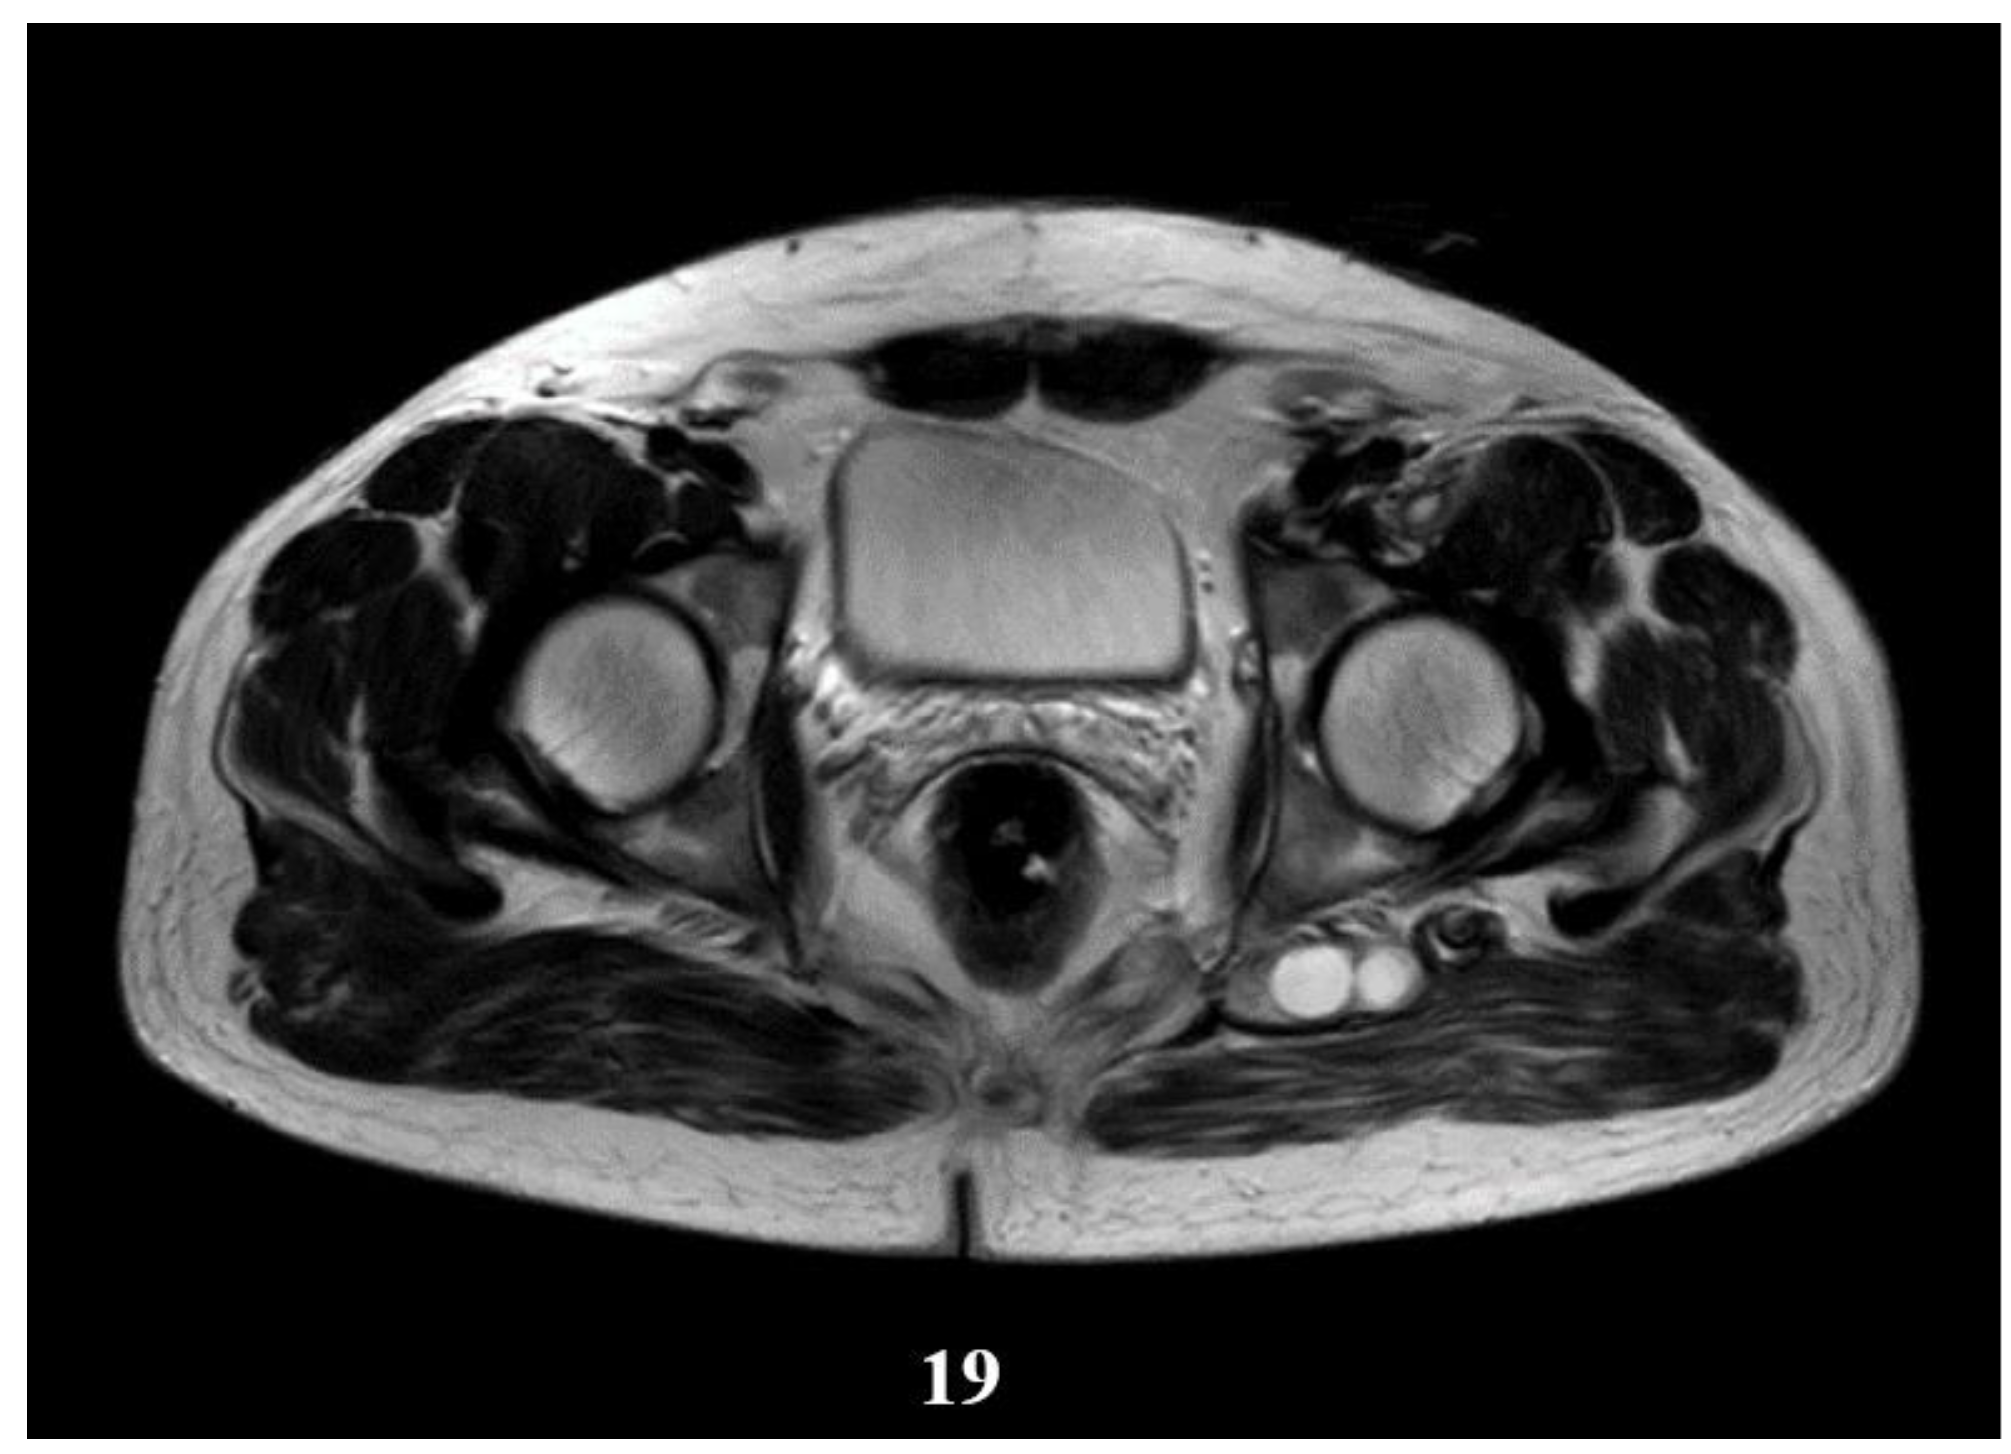

Deep from the gluteus maximus muscle on the left side, there are multiloculated, multiple septate intralesional, relatively well delimited areas, which seem to communicate both with each other and with lesions of a similar appearance located in the thickness and adjacent to the quadratus femoris muscle on the left side, with total dimensions in the coronal plane of approximately 11.3/6.4 cm, with the most likely appearance of parasitic cysts (Figure 19, Figure 20 and Figure 21).

Figure 19.

T2W sequence, axial—Postoperative residual hydatid cyst located at the level of the left psoas muscle and deep to the left gluteus maximus muscle (part 1).